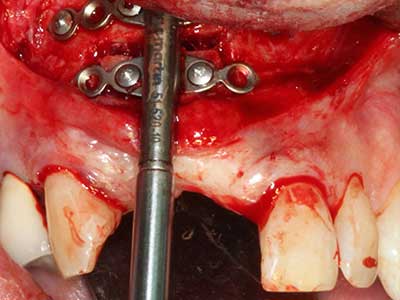

Fig. 18: Preparation of a cortical cover with the piezo bone saw (Piezomed, W&H).

Fig. 19: Surgical site after neurolysis and removal of osteoma.

Fig. 20: The removed bone cover is re-adapted and fixed with an osteosynthesis screw (KLS Martin, Tuttlingen).